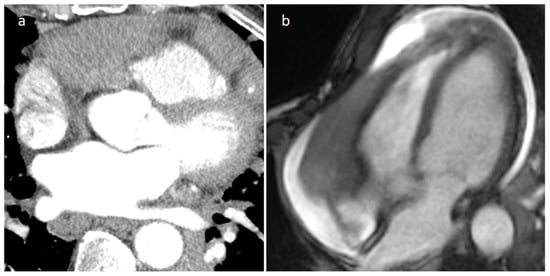

3.4. Pericardial Cyst

| Pericardial cyst | Adulthood | Right pericardiophrenic angle | Asymptomatic | Fluid-filled, thin-walled, homogeneous, no internal enhancement | Low echodensity | Hypodense well-defined lesion with a wall | Hypo T1w, hyper T2w, no internal enhancement |